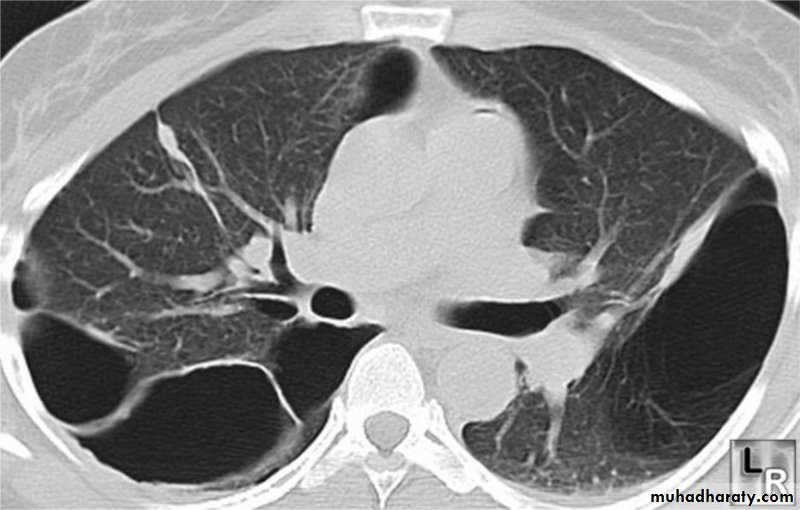

CT of chest;

Is useful in distinguishing bullae from pleural air.